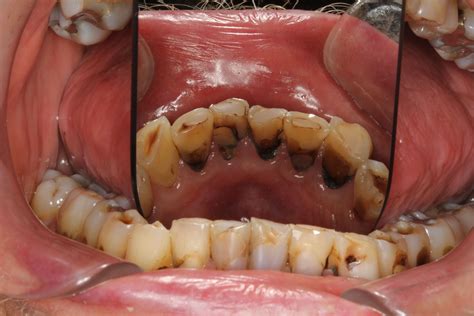

Xerostomia Causes Symptoms Treatment Xerostomia

Xerostomia Causes Symptoms Treatment Xerostomia